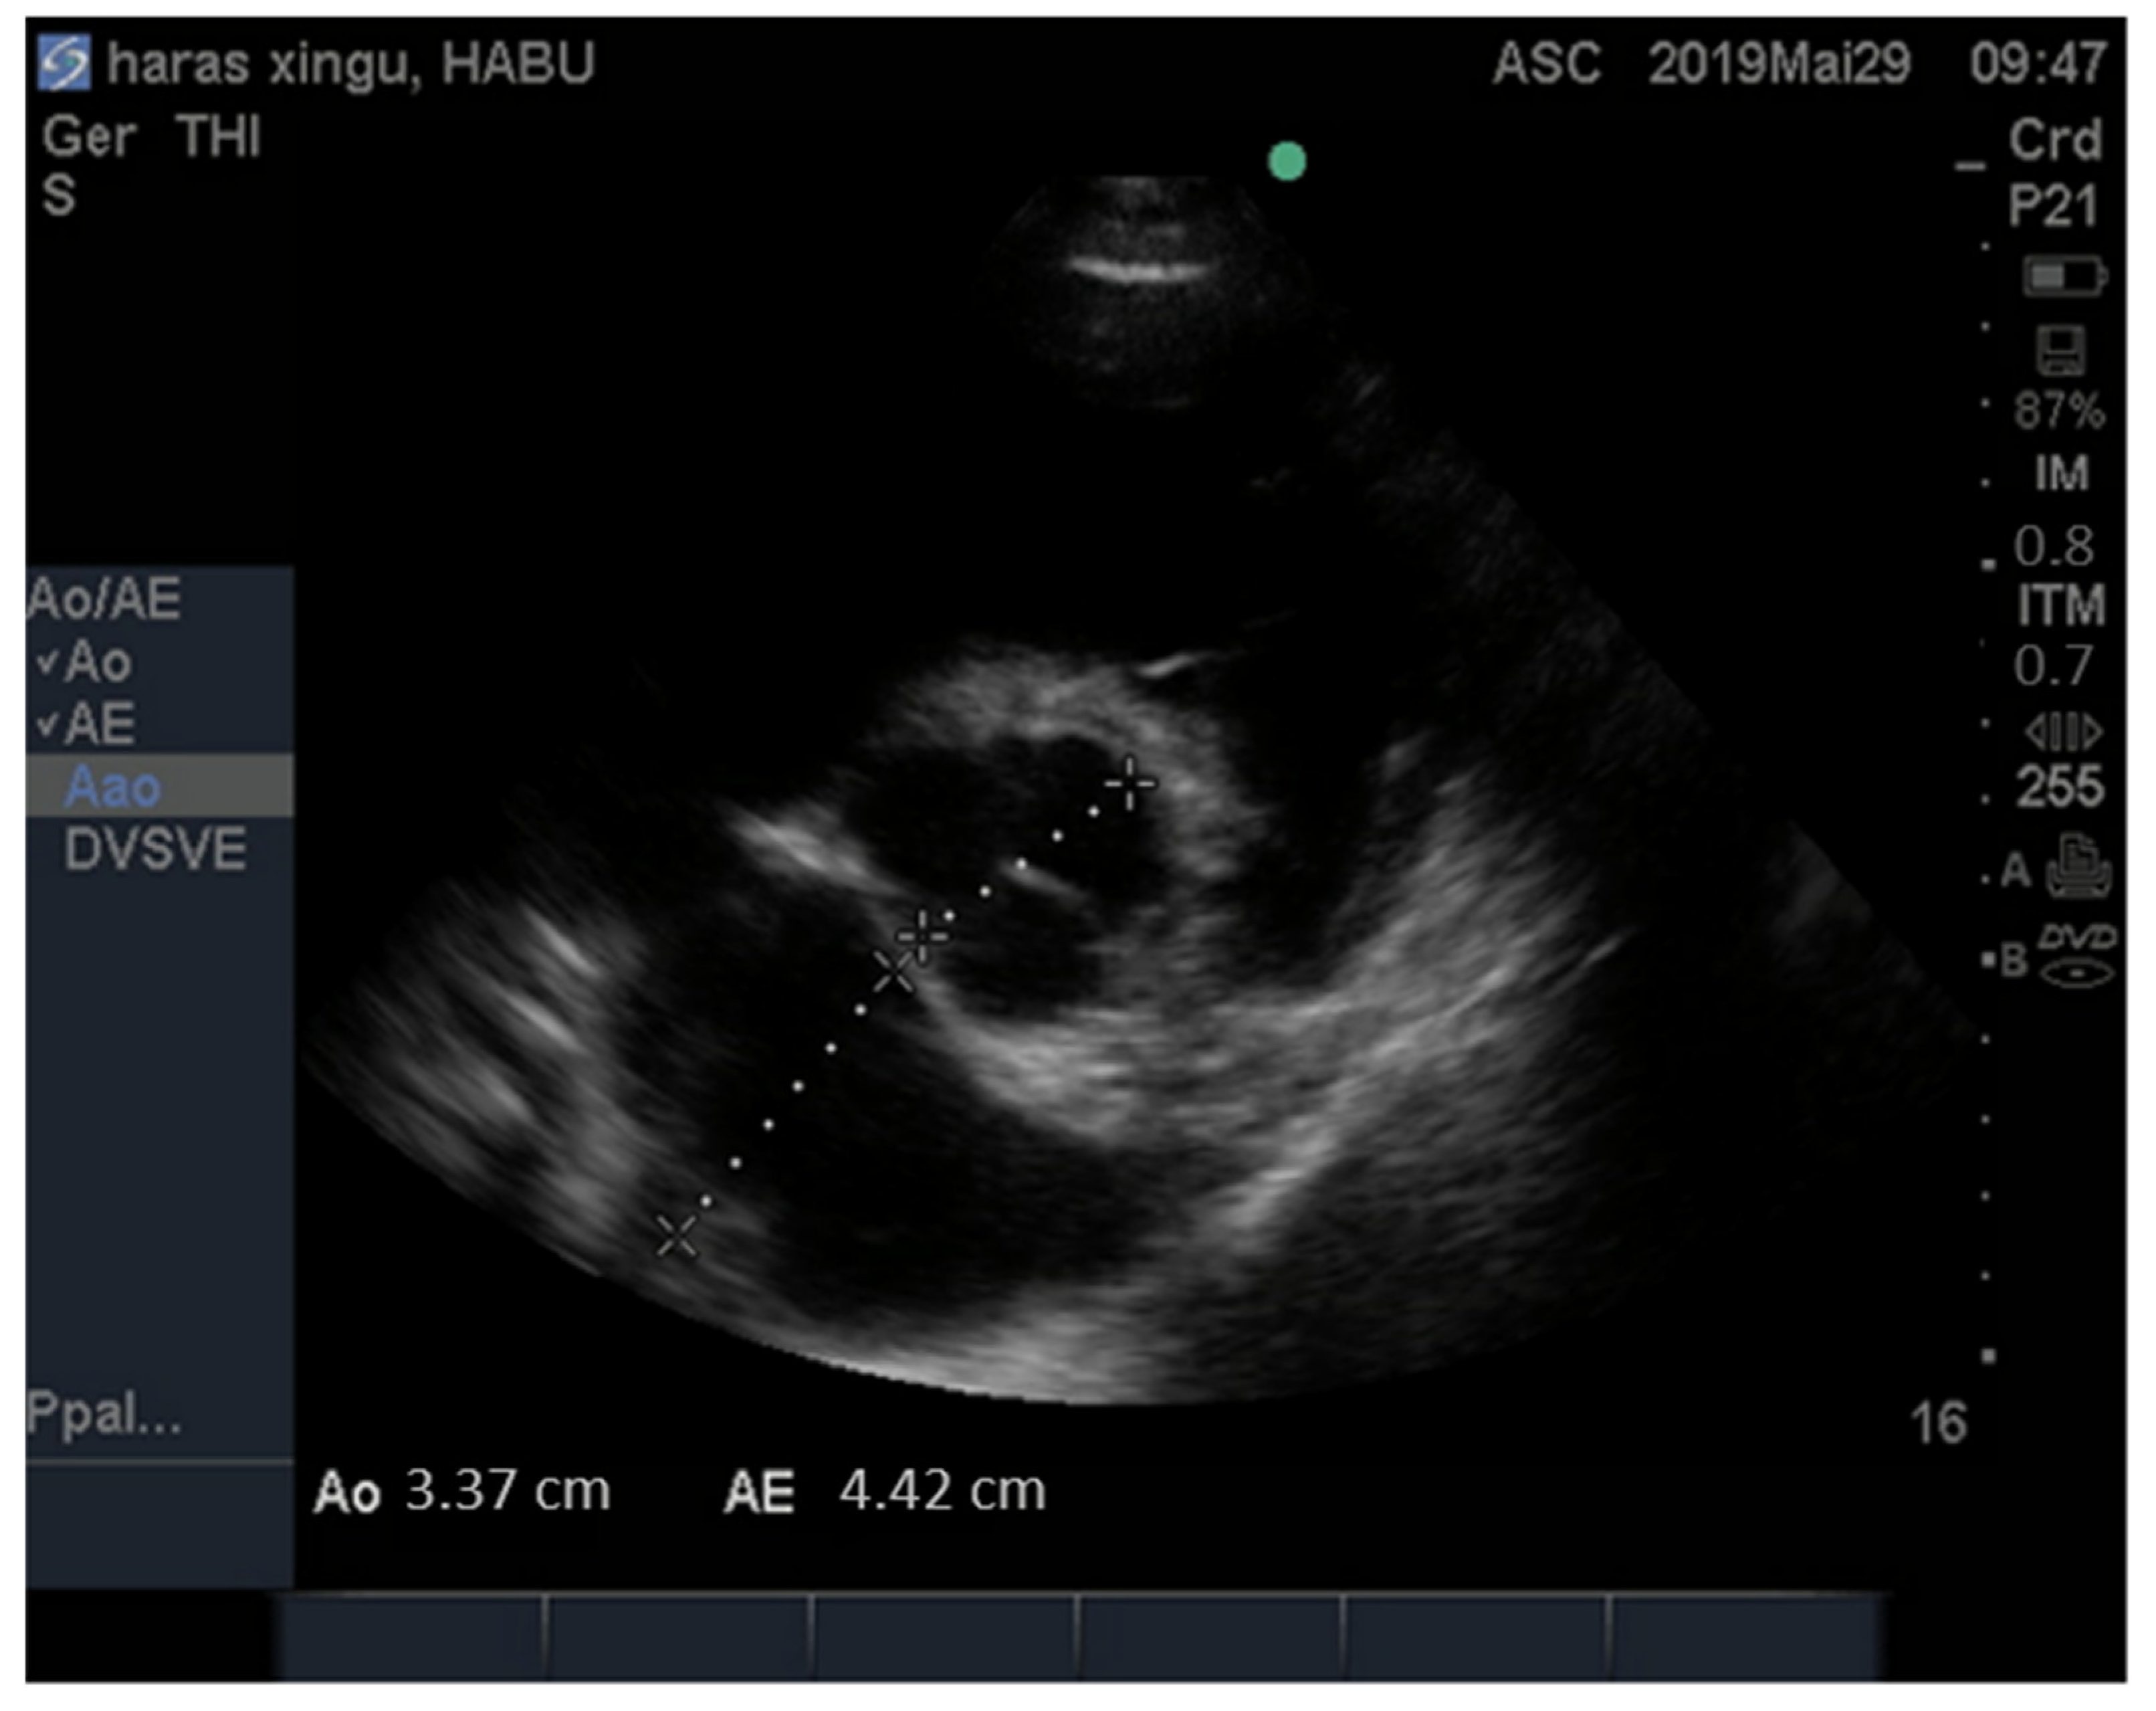

| IVSd (cm) | 1.74 ± 0.34 | 1.26 | 2.59 |

| LVIDd (cm) | 6.80 ± 1.08 | 4.60 | 9.17 |

| LVFWd (cm) | 1.73 ± 0.33 | 1.17 | 2.67 |

| IVSs (cm) | 3.05 ± 0.55 | 1.83 | 4.59 |

| LVIDs (cm) | 4.07 ± 0.71 | 2.45 | 5.47 |

| LVFWs (cm) | 2.59 ± 0.46 | 1.77 | 3.84 |

| RIVDd (cm) | 1.81 ± 0,61 | 1.0 | 3.74 |

| EF (%) | 68.82 ± 7.09 | 53.00 | 86.00 |

| FS (%) | 39.92 ± 5.99 | 27.90 | 55.80 |

| LA (cm) | 5.27 ± 0.64 | 4.03 | 6.51 |

| Ao (cm) | 4.03 ± 0.59 | 2.67 | 5.14 |

| LA/Ao | 1.31 ± 0.14 | 1.02 | 1.67 |

| Pulmonary diameter | 3.28 ± 0.45 | 2.25 | 4.30 |

| Aortic diameter | 4.04 ± 0.59 | 2.70 | 5.17 |

| Pul./Ao | 0.82 ± 0.10 | 0.66 | 1.35 |

| Pul.Veloc. (cm/s) | 91 ± 14.71 | 64.60 | 135.00 |

| Pul.Gr. Pres.(mmHg) | 3.39 ± 1.11 | 1.67 | 7.29 |

| Aortic Veloc. (cm/s) | 87.60 ± 14.95 | 60.30 | 130.60 |

| Ao.Gr. Pres. (mmHg) | 3.13 ± 1.06 | 1.45 | 6.82 |